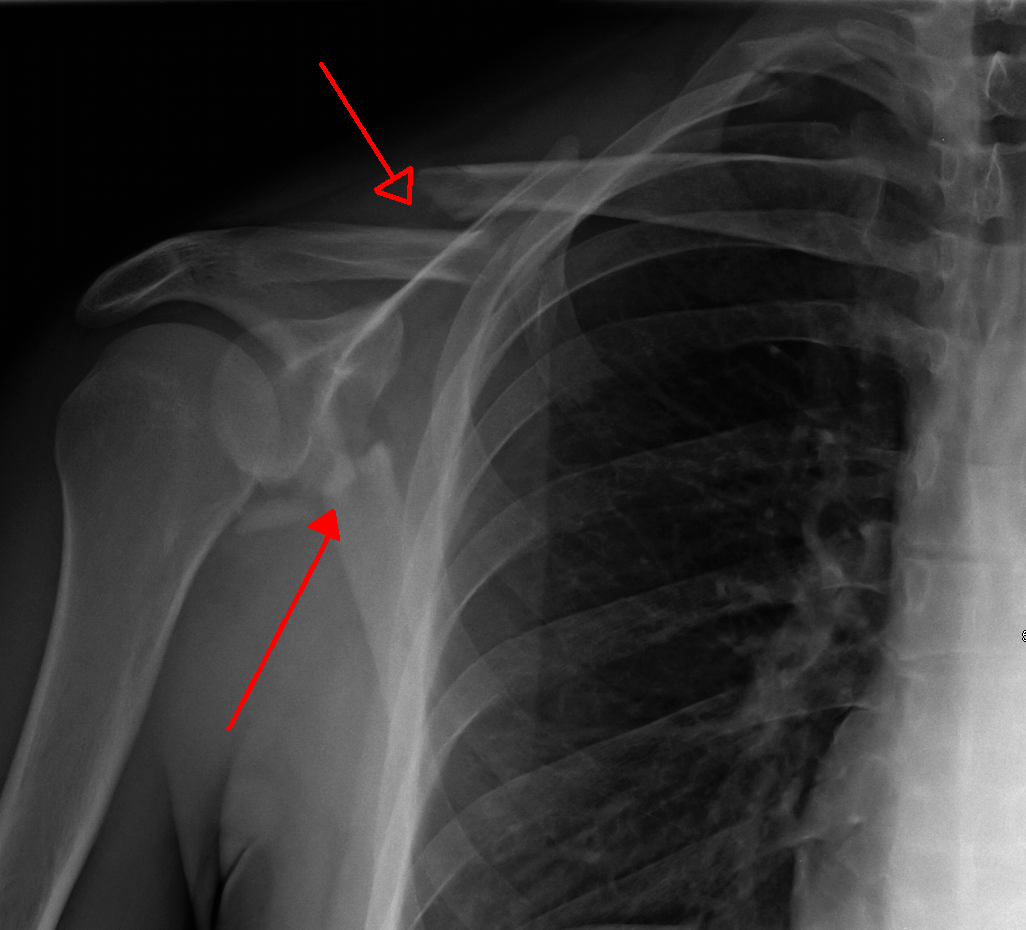

Collar bone fracture, Xray Stock Image C021/2246 Science Photo Can You Fracture Your Collarbone Without Knowing Clavicle fractures in the older person (collar bone fracture) (conservatively managed fragility fracture of the clavicle). A broken collarbone, or clavicle fracture, is a break in one of two long, thin bones that connect the breastbone to your shoulder. You may have broken your collarbone if you've been injured and your shoulder: A clavicle fracture can take between 6 to. Can You Fracture Your Collarbone Without Knowing.